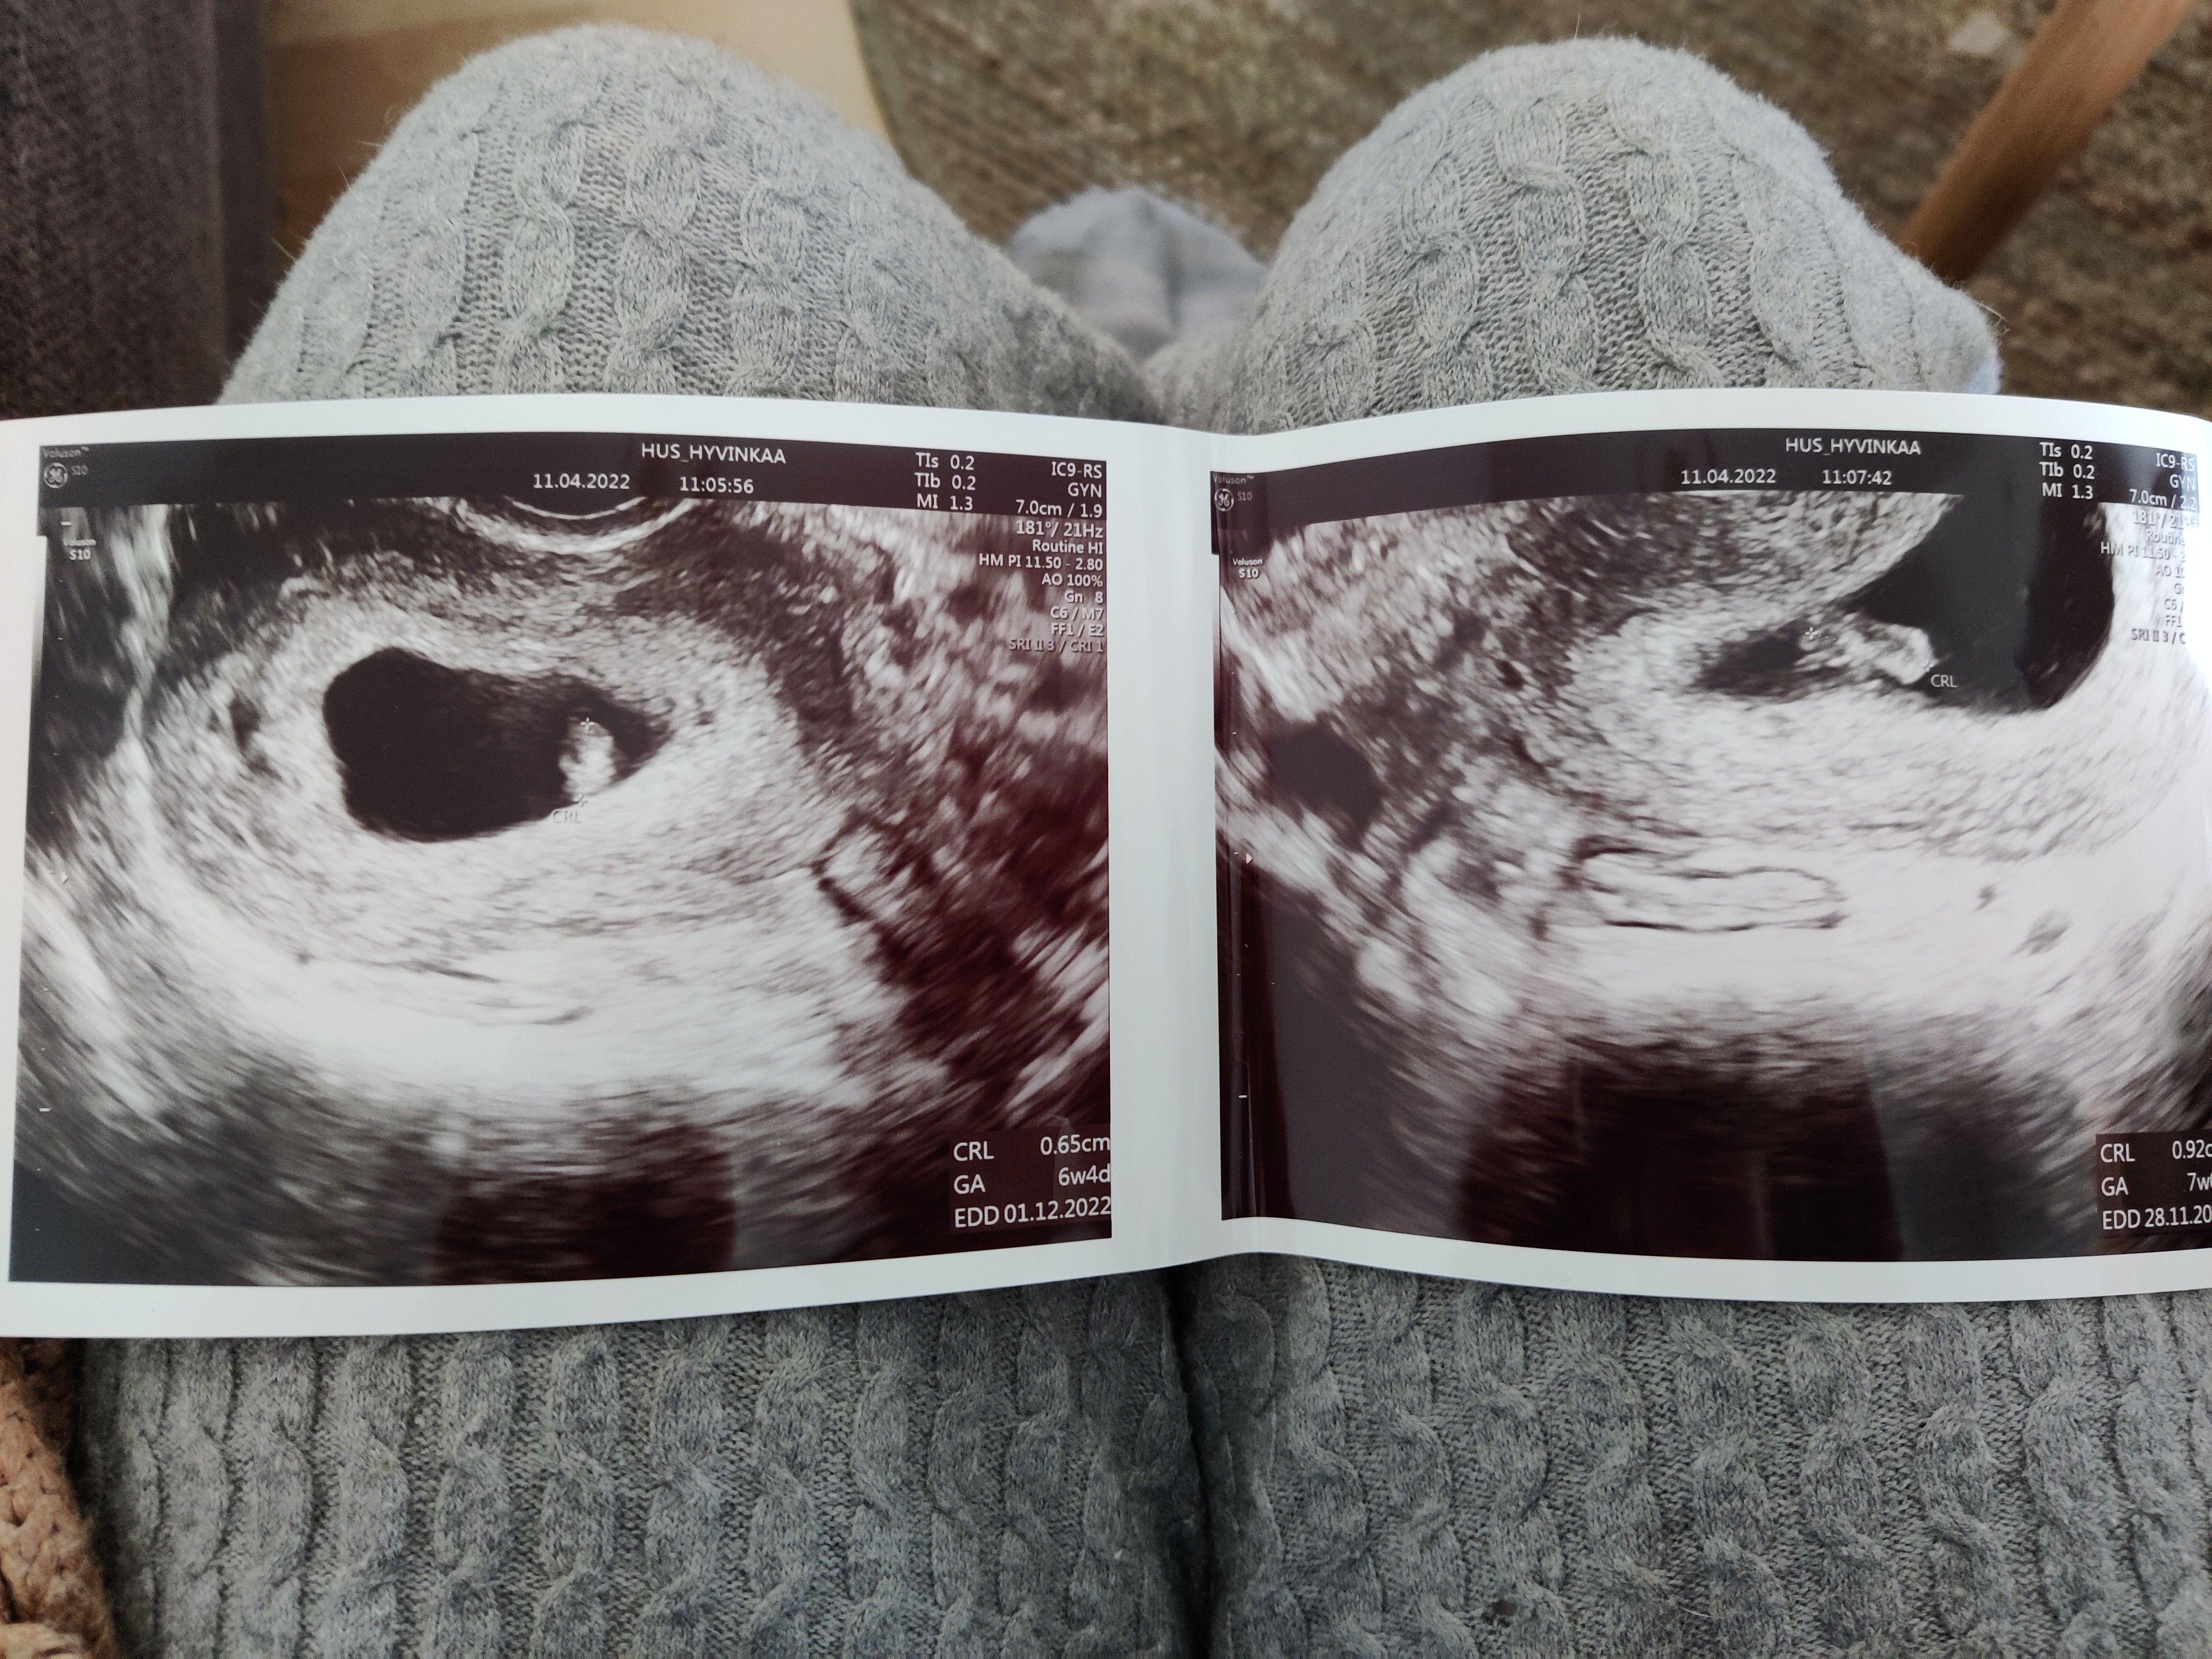

Koko vastasi pienimmän mitan mukaan 6+4 ja suurimman mitan mukaan 7+0. (Edit. Ovulaation mukaan siis 6+5 tänään) En voi uskoa tätä

Ja ultrakuulumiset! Täntäntääää... Kyllä siellä juku sentään oli sykeKoko vastasi pienimmän mitan mukaan 6+4 ja suurimman mitan mukaan 7+0. (Edit. Ovulaation mukaan siis 6+5 tänään) En voi uskoa tätä

Jotain kommentoi kohdun muodosta, että on vähän hassu. "Kaksisarvinen" tms.

Siitä syystä luuli ensin, että ois kaks alkiota siellä, mut yks sentäs vaan!

Kaikki näytti kuulemma normaalilta. Ei hematoomaakaan, mikä viime raskaudessa oli. Oon tosi yllättynyt, mutta onnellinen!